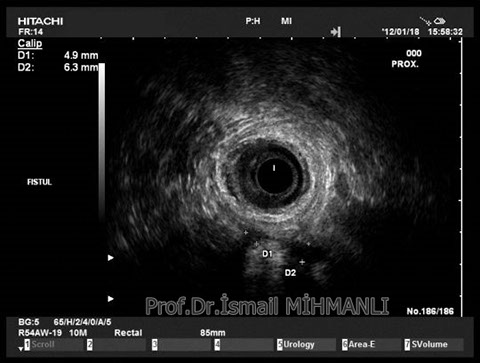

PERİANAL FİSTÜLLER Perianal fistül ve abselerin intersfinkterik anal bez iltihabından kaynaklandığı düşünülmektedir. Crohn hastalarında perianal enflamatuvar hastalık sıktır. İntersfinkterik mesafedeki enfeksiyon yukarıda rektuma, aşağıda cilde, yanlarda dış sfinkteri geçerek iskiyoanal mesafeye uzanabilir. Primer fistülün sfinkterler ile ilişkisini ve abse veya sekonder dal varlığını ameliyat öncesi bilmek, tedavi planı açısından önemlidir. İskiyoanal ve iskiyorektal mesafe tutulmamışsa hastalık daha kolay tedavi edilir. Bu mesafelerde abse veya sekonder bir dal varsa fistül komplekstir ve tedavisi kompleks olmayan fistüle göre değişik olabilir. Bundan dolayı, primer fistül traktı anatomik yerleşimine göre geleneksel olarak sınıflandırılır. Bu sınıflama dörde ayrılır: 1- İntersfinkterik (iç ve dış sfinkter arasında), 2- Transsfinkterik (dış sfinkteri geçerek iskiyoanal veya iskiyorektal mesafeye ulaşmış), 3- Suprasfinkterik (intersfinkterik plandan yukarı doğru uzanan traktüs puborektal kasın Genel Gaz ve Dışkı Kaçırma (Anal İnkontinans) Perianal Fistüller Rektal Tümörler Anal Tümörler Kabızlık Yazılarımız üstündeki bir seviyeden yana kıvrılarak tekrar aşağıya iskiyoanal mesafeye uzanmış), 4- Ekstrasfinkterik (sfinkterlerin dış tarafında rektumdan direkt olarak perianal cilde uzanan traktüs). Endoanal ultrason ile hem primer fistül, hem de varsa sekonder dal ve abse doğru bir şekilde tanınır. Endoanal ultrason ile fistülün anal kanala açılan kısmını (iç uç) görmek kolaydır. Bu hastalarda sfinkter defektlerine de rastlanmaktadır. Sfinkter defekti endoanal ultrason ile kolaylıkla tespit edilir. (bkz. anal inkontinans) Perianal fistül şikayeti olan hastaların az kısmında endoanal ultrason ile bir şey görülemez ise endoanal ultrason probuna ek olarak lineer prob ile anal kanal çevresine bakmak yararlıdır. Çünkü anal kanal bileşenlerinin uzağındaki bir enflamasyon ancak bu problar ile tanınabilir.

İntersfİnkterİk fİstül TRANSSFİNKTERİK FİSTÜL